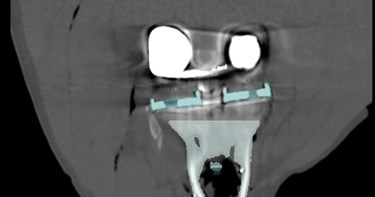

Adequate fixation of a revision (knee)implant is crucial for its survival. However, this is challenging due to bone loss and poorer quality of the remaining bone. By preoperatively examining the anatomy, reason for revision, and the amount and quality of bone before surgery, a tailored treatment can be developed to ensure proper fixation. The use of 3D CT-based migration analysis can help determine whether the fixation is adequate.